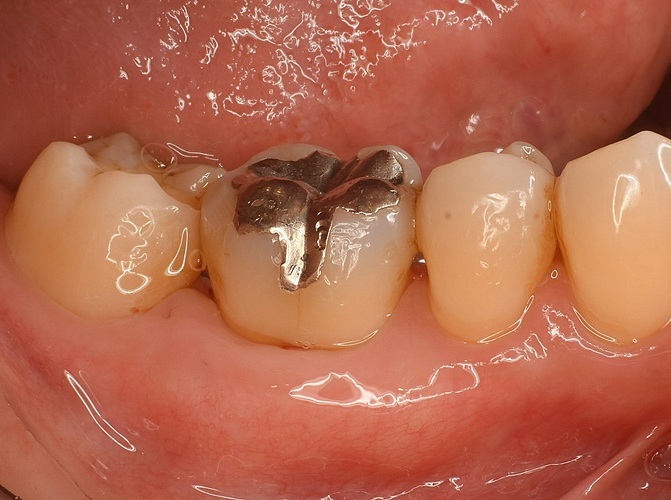

Case2

術前

術中

術後

| 治療説明 | 右下6に重度の歯周病があり、通常の歯周治療でも改善しませんでした。歯周組織再生療法を行い、吸収してしまった骨を再生し、今後の歯周病の進行リスクを減らす事ができました。歯肉退縮もあったため同時に結合組織を移植し、骨と歯肉の再生を同時に行っています。 |

| 治療回数・期間 | 6ヶ月 |

| 副作用とリスク | 手術後に出血、腫脹、疼痛が生じることがあります。手術後は術部の創傷安定のためにブラッシング制限、食事制限があります。手術が複数回となることがあります。 |

| 料金(税込) | 再生療法:165,000円 結合組織移植:55,000円 総額:220,000円 |